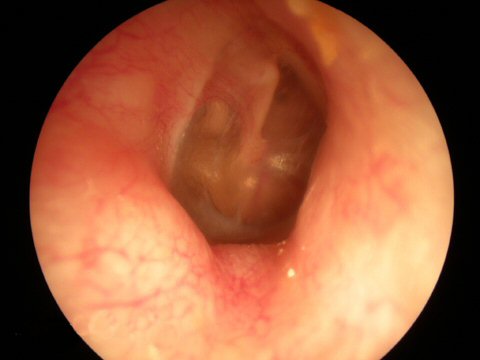

External Otitis - Swimmers Ear This is an infection of the ear canal itself. Notice the swelling of the ear canal.

Fungal infection of the ear canal